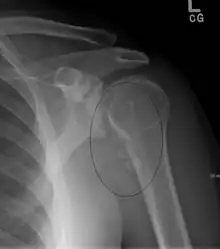

Radiography

Typical finding is of multiple, smooth, oval-shaped calcified masses within the joint space or bursa. They have a characteristic popcorn-ball appearance of calcified cartilage. With serial imaging, masses may be found to change in size, disappear, or migrate to recessed areas of the joint. They may pass from the main joint cavity into a neighboring synovial cyst. For this reason, a mass may not be appreciated within the actual joint space itself.

Additional radiographic findings include joint effusion and degenerative changes such as joint space narrowing, subchondral sclerosis, and osteophyte formation.

Intra-articular bodies in SOC typically have popcorn calcification, with a dense sclerotic border with radiolucent central region. This distinct radiographic appearance sets it apart from other causes of intra-articular bodies. Number and size of intra-articular bodies can prove helpful as well. SOC typically presents as multiple intra-articular bodies. Few or isolated intra-articular bodies are more consistent with trauma or osteoarthritis.